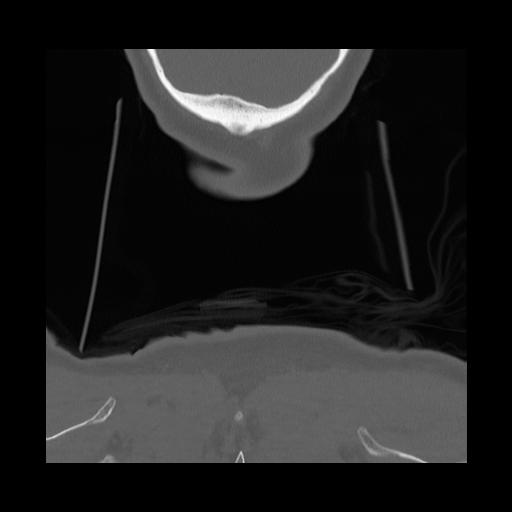

16 HUESO,,Coronal,2.000,HUESO,Coronal,